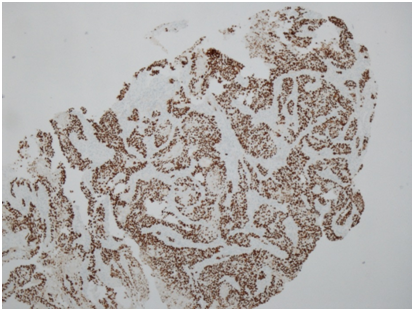

He then underwent full colonoscopic examination, which revealed a large friable and bleeding mass within the caecum (Figure 1). There were no macroscopic areas of ulceration elsewhere within the colon. Histology of the caecal mass reported a moderately differentiated squamous cell carcinoma (Figure 2A). Subsequent immunohistochemistry analysis showed that the tumour cells were strongly positive for CK5/6 and p63, but CK20 and CDX2 negative, consistent with a diagnosis SCC (Figure 2B). Coinciding with this, tumour markers were found to be elevated (CEA 16ug/L).

Figure 2B p63 immunohistochemistry (x40 magnification) demonstrating diffuse nuclear p63 immunoexpression within tumour cells, which is typical of SCC and absent in adenocarcinoma.